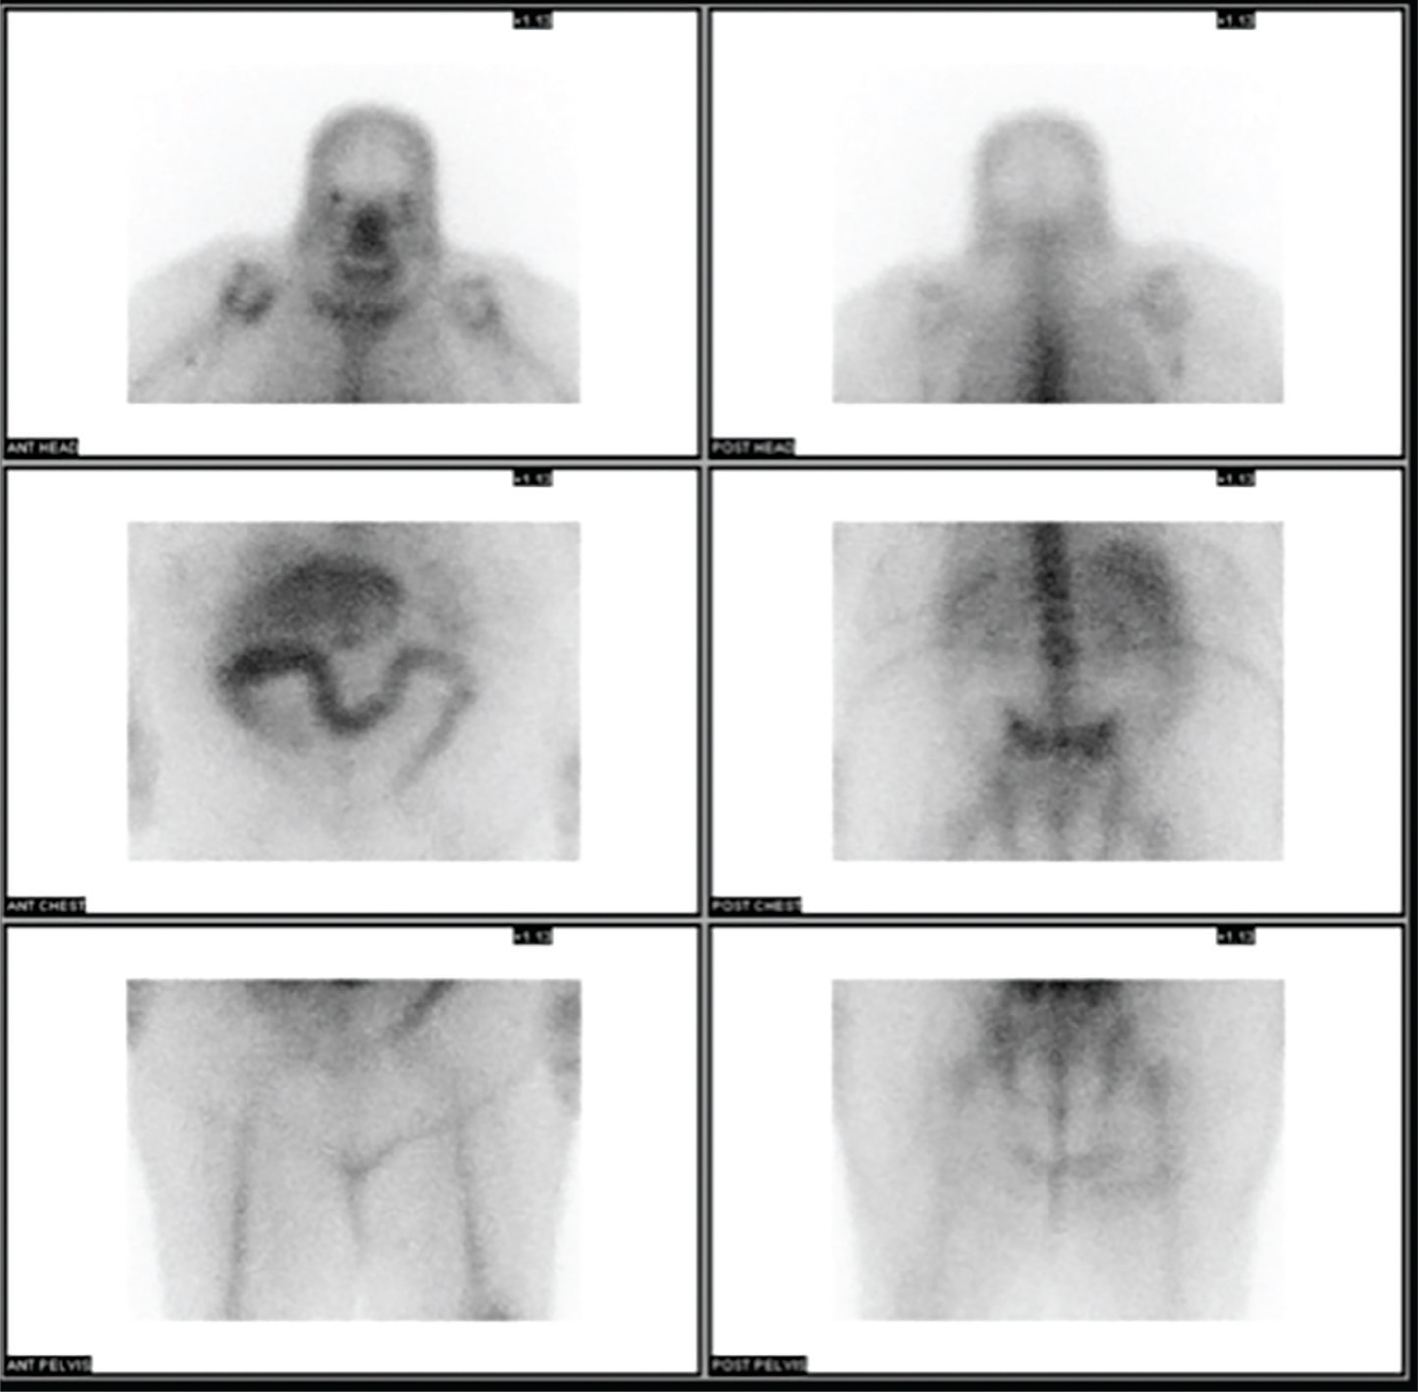

The mechanism of localization of 67Ga-citrate is not well understood but has been postulated to reflect iron metabolism. 67Ga-citrate has a half-life of 78 hours, is cyclotron produced, and decays by electron capture, with the critical organ being the colon. Its photopeaks are 93, 185, 300 and 394 keV. Given the long half-life, this agent is not recommended for pediatric patients. Historically, 67Ga-citrate has been used for the imaging of lymphoma, which occasionally helps in the incidental detection of other tumors. In the past, 67Ga-citrate was the preferred agent for the study of sarcoidosis, which is now better evaluated with 18F-fluorodexyglucose (18F-FDG) positron emission tomography (PET). In addition, 67Ga-citrate could be used in the setting of vertebral osteomyelitis since it has better overall performance, however, 67Ga-citrate is falling out of favor due to its long half-life, relatively high radiation dose, and unfavorable imaging characteristics (1, 2). Figure 1 shows normal biodistribution of 67Ga-citrate.

Fig 1

Figure 1 Normal distribution of 67Ga-citrate. Anterior and posterior planar images of the head, neck, chest, abdomen, pelvis and proximal lower extremities demonstrate normal biodistribution of 67Ga-citrate.